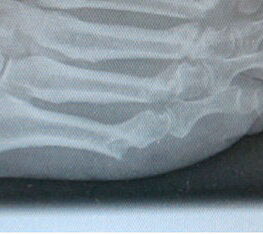

Lagerung des Patientenfußes auf dem Röntgendetektor des Bildversärkers.

Abbildung 1

Abwaschen und steriles Abdecken des Fußes und Sprung­gelenkes. Die Operation erfolgt normalerweise ohne Blut­sperre. Der Patientenfuß ragt über das distale Ende des Op Tisches hinaus. Der Unterschenkel wird auf einem Beinhalter gelagert. Der Fuß selber wird auf dem Röntgen­detektor des am Fußende stehenden Bildwandlers aufgesetzt. Der Bild­wandler wird zum Patienten geneigt (Abb.1).

Während der Operation kann der Operateur, der hinter dem Bildwandler steht oder sitzt, ohne Positionsänderung des Fußes die notwendigen Röntgenkontrollen durchführen. Auch aus Strahlenschutzgründen ist die Verwendung eines Mini-C-Bogens vorteilhaft.